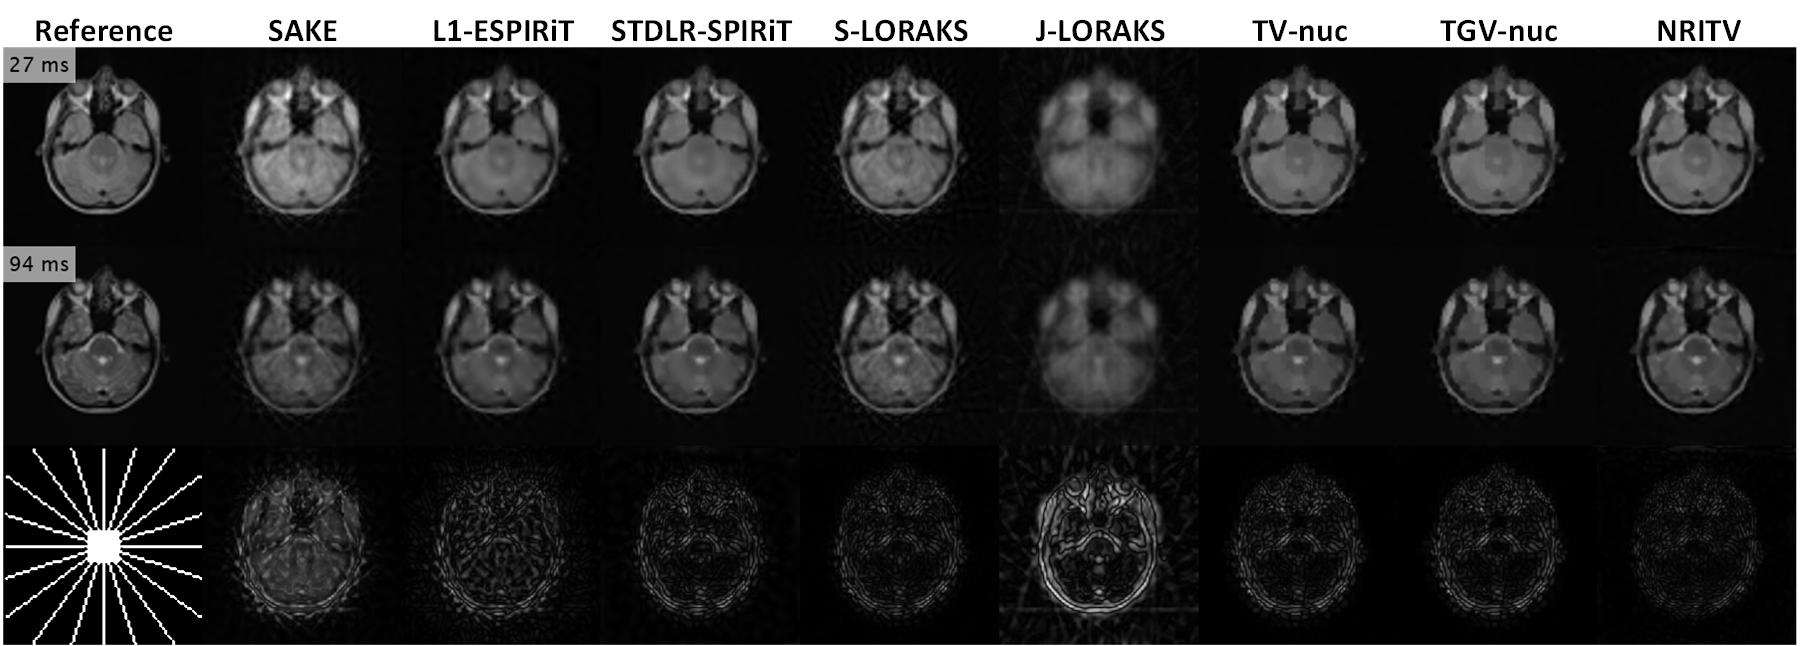

Refer to caption

Figure 15: Reconstruction results for a radially sampled (R=7𝑅7R=7) double-echo (272727 and 949494 ms) slice from the in-vivo brain data in reference [11]. It can be seen in the error maps that most of the methods output acceptable results with NRITV being superior. As usual, SENSE-type methods used perfect maps and NRITV used ESPIRiT-estimated maps (18%percent1818\% error). Compared methods’ parameters were mostly the same as the breast experiment.